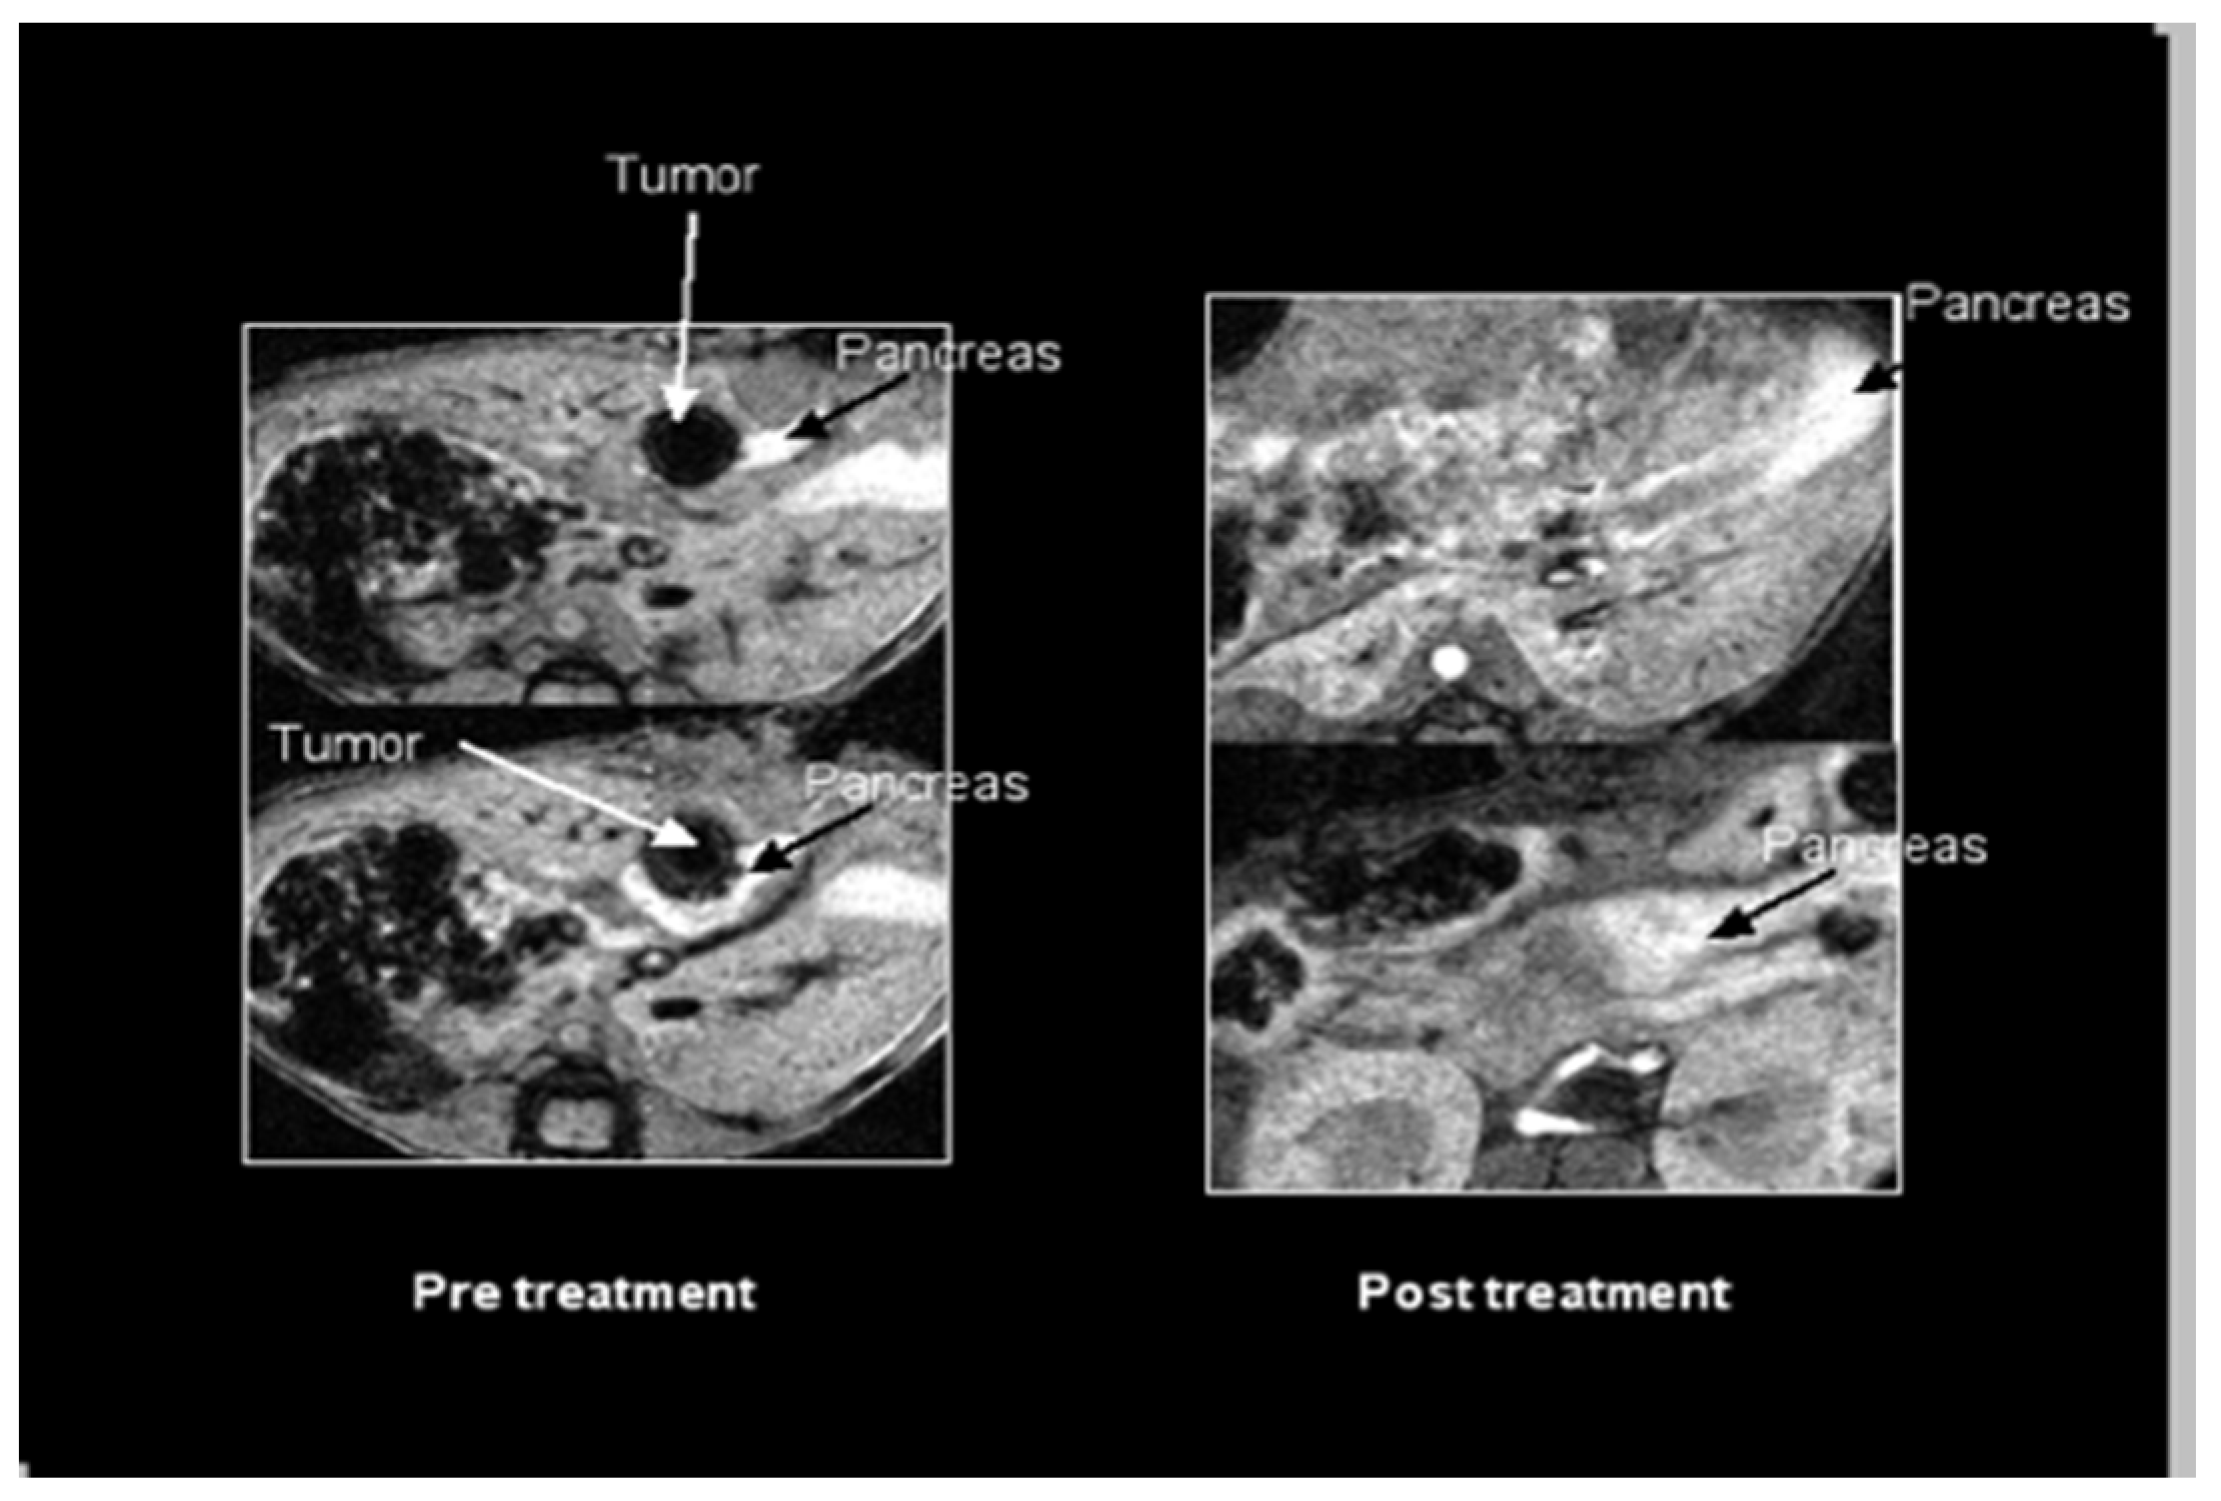

2.1. SV Vectors Can Generate Regression of Human Pancreatic Tumors in an SCID Mouse Model